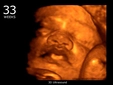

23 haftalık gebelik, hamileliğin ikinci trimesterinin sonlarına yaklaşıldığı bir dönemi ifade eder. Bu süre zarfında, hem anne hem de bebek için birçok önemli gelişim ve değişiklik yaşanmaktadır. Bu makalede, 23 haftalık gebelik dönemindeki fiziksel ve duygusal değişimlerin yanı sıra, bebeğin gelişimi, anne adayının sağlığı ve dikkat edilmesi gereken hususlar ele alınacaktır. Bebeğin Gelişimi23 haftalık gebelikte bebek, hızla büyümeye devam etmekte ve birçok önemli gelişim sürecinden geçmektedir. Bu dönemde, bebeğin gelişimiyle ilgili bazı önemli noktalar şunlardır: